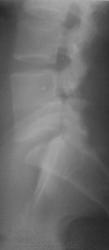

Мужчина 35 лет. Жалобы на дискомфорт в поясничном отделе. Из анамнеза - травма в возрасте 6 лет (падение с высоты на ягодицы).

Конкресенция 4-5 позвонков.Дефицита высоты каждого из позвонков достоверно не вижу, диск резко гипоплазирован, сагиттальный размер не увеличен.Можно предположить травматического характера, но врожденный я бы  полностью не исключала.

Не думаю, что причина в травме. Скорее всего врождённое, хотя остистые не изменены.

Я думаю причина в травме, тень от замыкательных пластин прослеживается.

Т.е. - изолированое травматическое поражение диска БЕЗ изменений формы позвонков?

Все правильно, по-моему, а остеохондроз как причина дискомфорта? Такие позвонки- это случайная интересная находка( коллеге +), и врожденный характер этих изменений, Вы, Helios, правильно полностью ПОДТВЕЖДАЕТЕ smiley. Тела позвонков не изменены - какая травма? Что, траматически срослисьsmiley? С исчезновением в никуда диска?smiley

Еще угловой деформации позвоночного столба на этом уровне нет.

А я так описал кифотическую деформацию...еще и высказал мнение о наличии признаков сужения спинномозгового канала...пусть и незначительном.